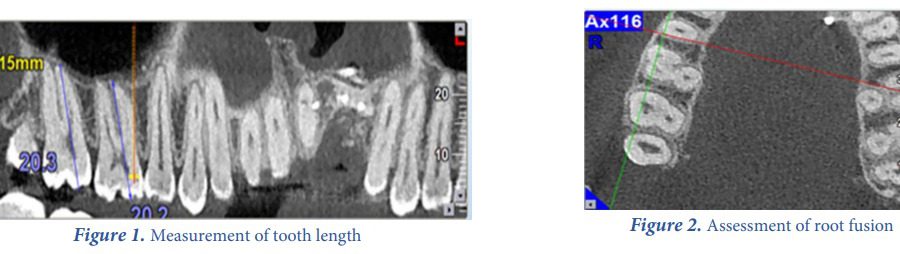

Root Canal Morphology of Maxillary Second Molars according to Age and Gender in a Selected Iranian Population : A Cone-Beam Computed Tomography Evaluation